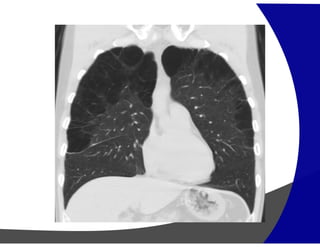

Fibrose Pulmonar

Achados por Imagem

• Raio – X – geralmente normal

Avançada – redução volumétrica e opacidade reticulares

subpleurais com gradiente de apresentação ápico-basais.

• TCAR

Redução volumétrica

Opacidades reticulares subpleurais

Faveolamento (macro)

Bronquiectasias de tração

Gradiente de envolvimento apico-basal

Heterogenicidade espacial e temporal de distribuição

Fibrose Pulmonar Achados porImagem • Raio – X – geralmente normal Avançada – redução volumétrica e opacidade reticulares subpleurais com gradiente de apresentação ápico-basais. • TCAR Redução volumétrica Opacidades reticulares subpleurais Faveolamento (macro) Bronquiectasias de tração Gradiente de envolvimento apico-basal Heterogenicidade espacial e temporal de distribuição